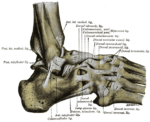

Правый голеностопный сустав, вид сбоку.

Большеберцовая и малоберцовая кости охватывают блок таранной кости наподобие вилки. Суставная капсула сзади и по бокам прикрепляется к краям сочленяющихся поверхностей, а спереди на полсантиметра отступает от них. Связки располагаются на боковых поверхностях сустава[3]:

• На внешней стороне сустава расположены передняя и задняя таранно-малоберцовые и пяточно-малоберцовая связки — все они расходятся веерообразно, начинаясь на латеральной лодыжке: передняя таранно-малоберцовая связка (лат. ligaméntum talofibuláre antérius) крепится к шейке таранной кости, задняя таранно-малоберцовая связка (лат. ligaméntum talofibuláre postérius) — к заднему отростку таранной кости, а пяточно-малоберцовая связка (лат. ligaméntum calcaneofibuláre) спускается вниз, оканчиваясь на наружной поверхности пяточной кости.

• На внутренней стороне голеностопного сустава расположена дельтовидная (медиальная) связка (лат. ligaméntum deltoídeum seu mediále), которая начинается на внутренней (медиальной) лодыжке и делится на четыре части:

• большеберцово-ладьевидная часть (лат. pars tíbionaviculáre) прикрепляется к ладьевидной кости стопы;

• большеберцово-пяточная (лат. pars tíbiocalcánea) крепится к пяточной кости;

• передняя и задняя большеберцово-таранные части (лат. pártes tíbiotaláres antérior et postérior), прикрепляющиеся к таранной кости.